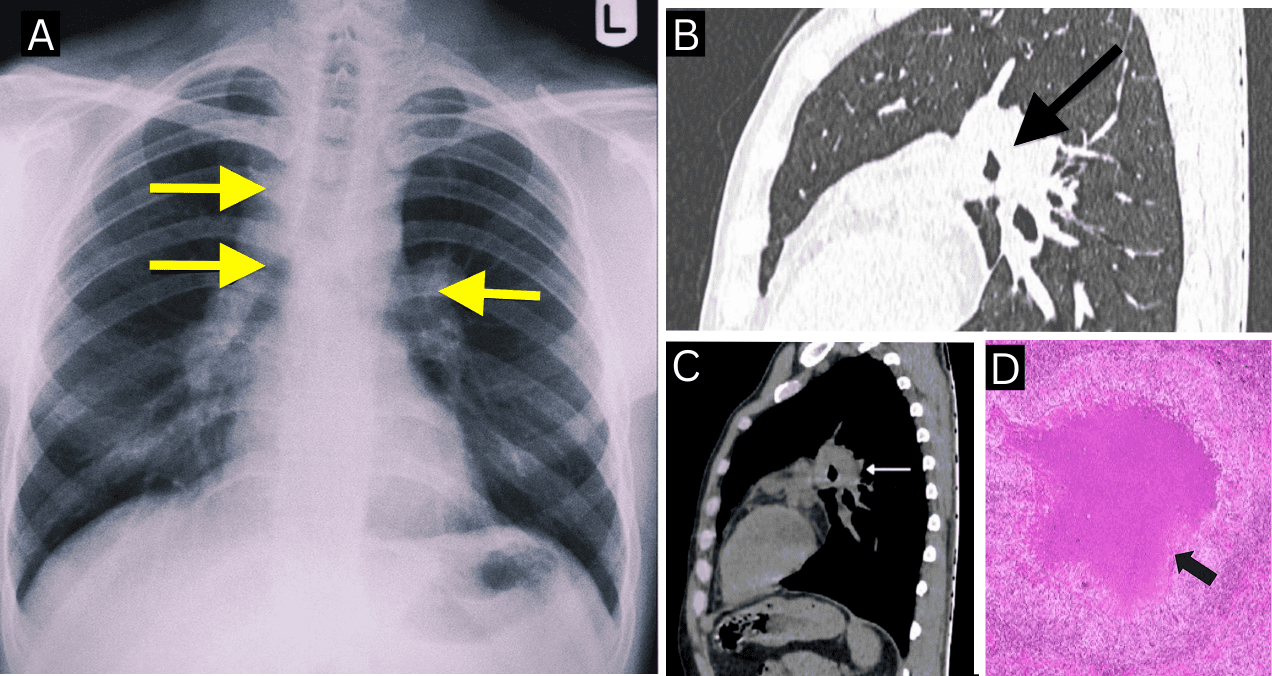

Una radiografía de tórax reveló prominencia hiliar bilateral y ensanchamiento del paratraqueal derecho. Con estos hallazgos, se procedió a realizar una tomografía computarizada (TC) de tórax, que evidenció adenopatías paratraqueales y subcarinales del lado derecho, con una configuración que llamó la atención del equipo médico: los ganglios linfáticos mostraban hipodensidad central con realce periférico, dispuestos de forma anular alrededor de la vía aérea. Este patrón, conocido como el signo de "Medu Vada", fue claramente identificado en la ventana mediastínica.

No se observaron lesiones cavitarias ni compromiso parenquimatoso pulmonar activo. Estos hallazgos orientaron el diagnóstico hacia una linfadenopatía mediastínica con necrosis central.

Los autores (Sivagnaname et al) destacan que este caso resalta el valor diagnóstico del signo de "Medu Vada", una configuración radiológica anular provocada por ganglios linfáticos agrandados que circunscriben la vía aérea central.

En las tomografías, los ganglios afectados por tuberculosis pueden adoptar esta morfología, producto de la necrosis central con realce periférico y la disposición anatómica que recuerda a la forma del popular alimento del sur asiático.

A diferencia de la clásica "rosquilla", el Medu Vada tiene un contorno más irregular, lo cual lo convierte en una analogía más precisa para describir la imagen de ganglios linfáticos conglomerados y lobulados. Esta referencia cultural también ha demostrado ser útil para facilitar el aprendizaje entre profesionales de la salud, sobre todo en regiones endémicas de tuberculosis.